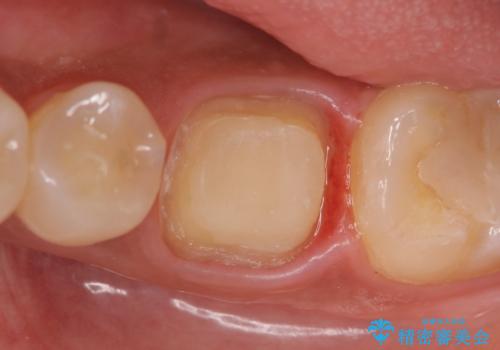

- 他院にて左下6の治療をしていたが、症状が引かないため当院にいらっしゃった方の症例です。

検査の結果左下6は神経が死んでいたため、根管治療を行いました。

その後症状の緩解を確認後、オールセラミッククラウンによる補綴を行いました。